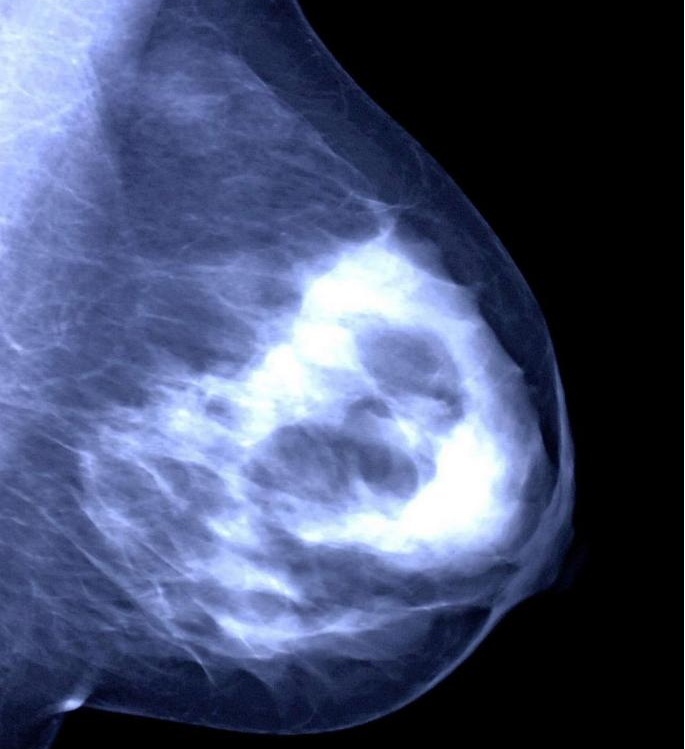

②乳腺钼靶:有点像给乳房拍“X 光片”,能发现一些超声看不到的细小钙化,对40岁以上女性筛查乳腺癌很有帮助。

2.恶性肿物:需要警惕的“坏分子”。

恶性肿物也就是乳腺癌,相对来说没那么常见,但需要高度重视。它摸起来通常比较硬,边界不清楚,形状不规则,用手推不太容易活动,而且大多不会疼,悄悄就长起来了。不过大家别害怕,只要发现得早,及时治疗,效果还是很好的。